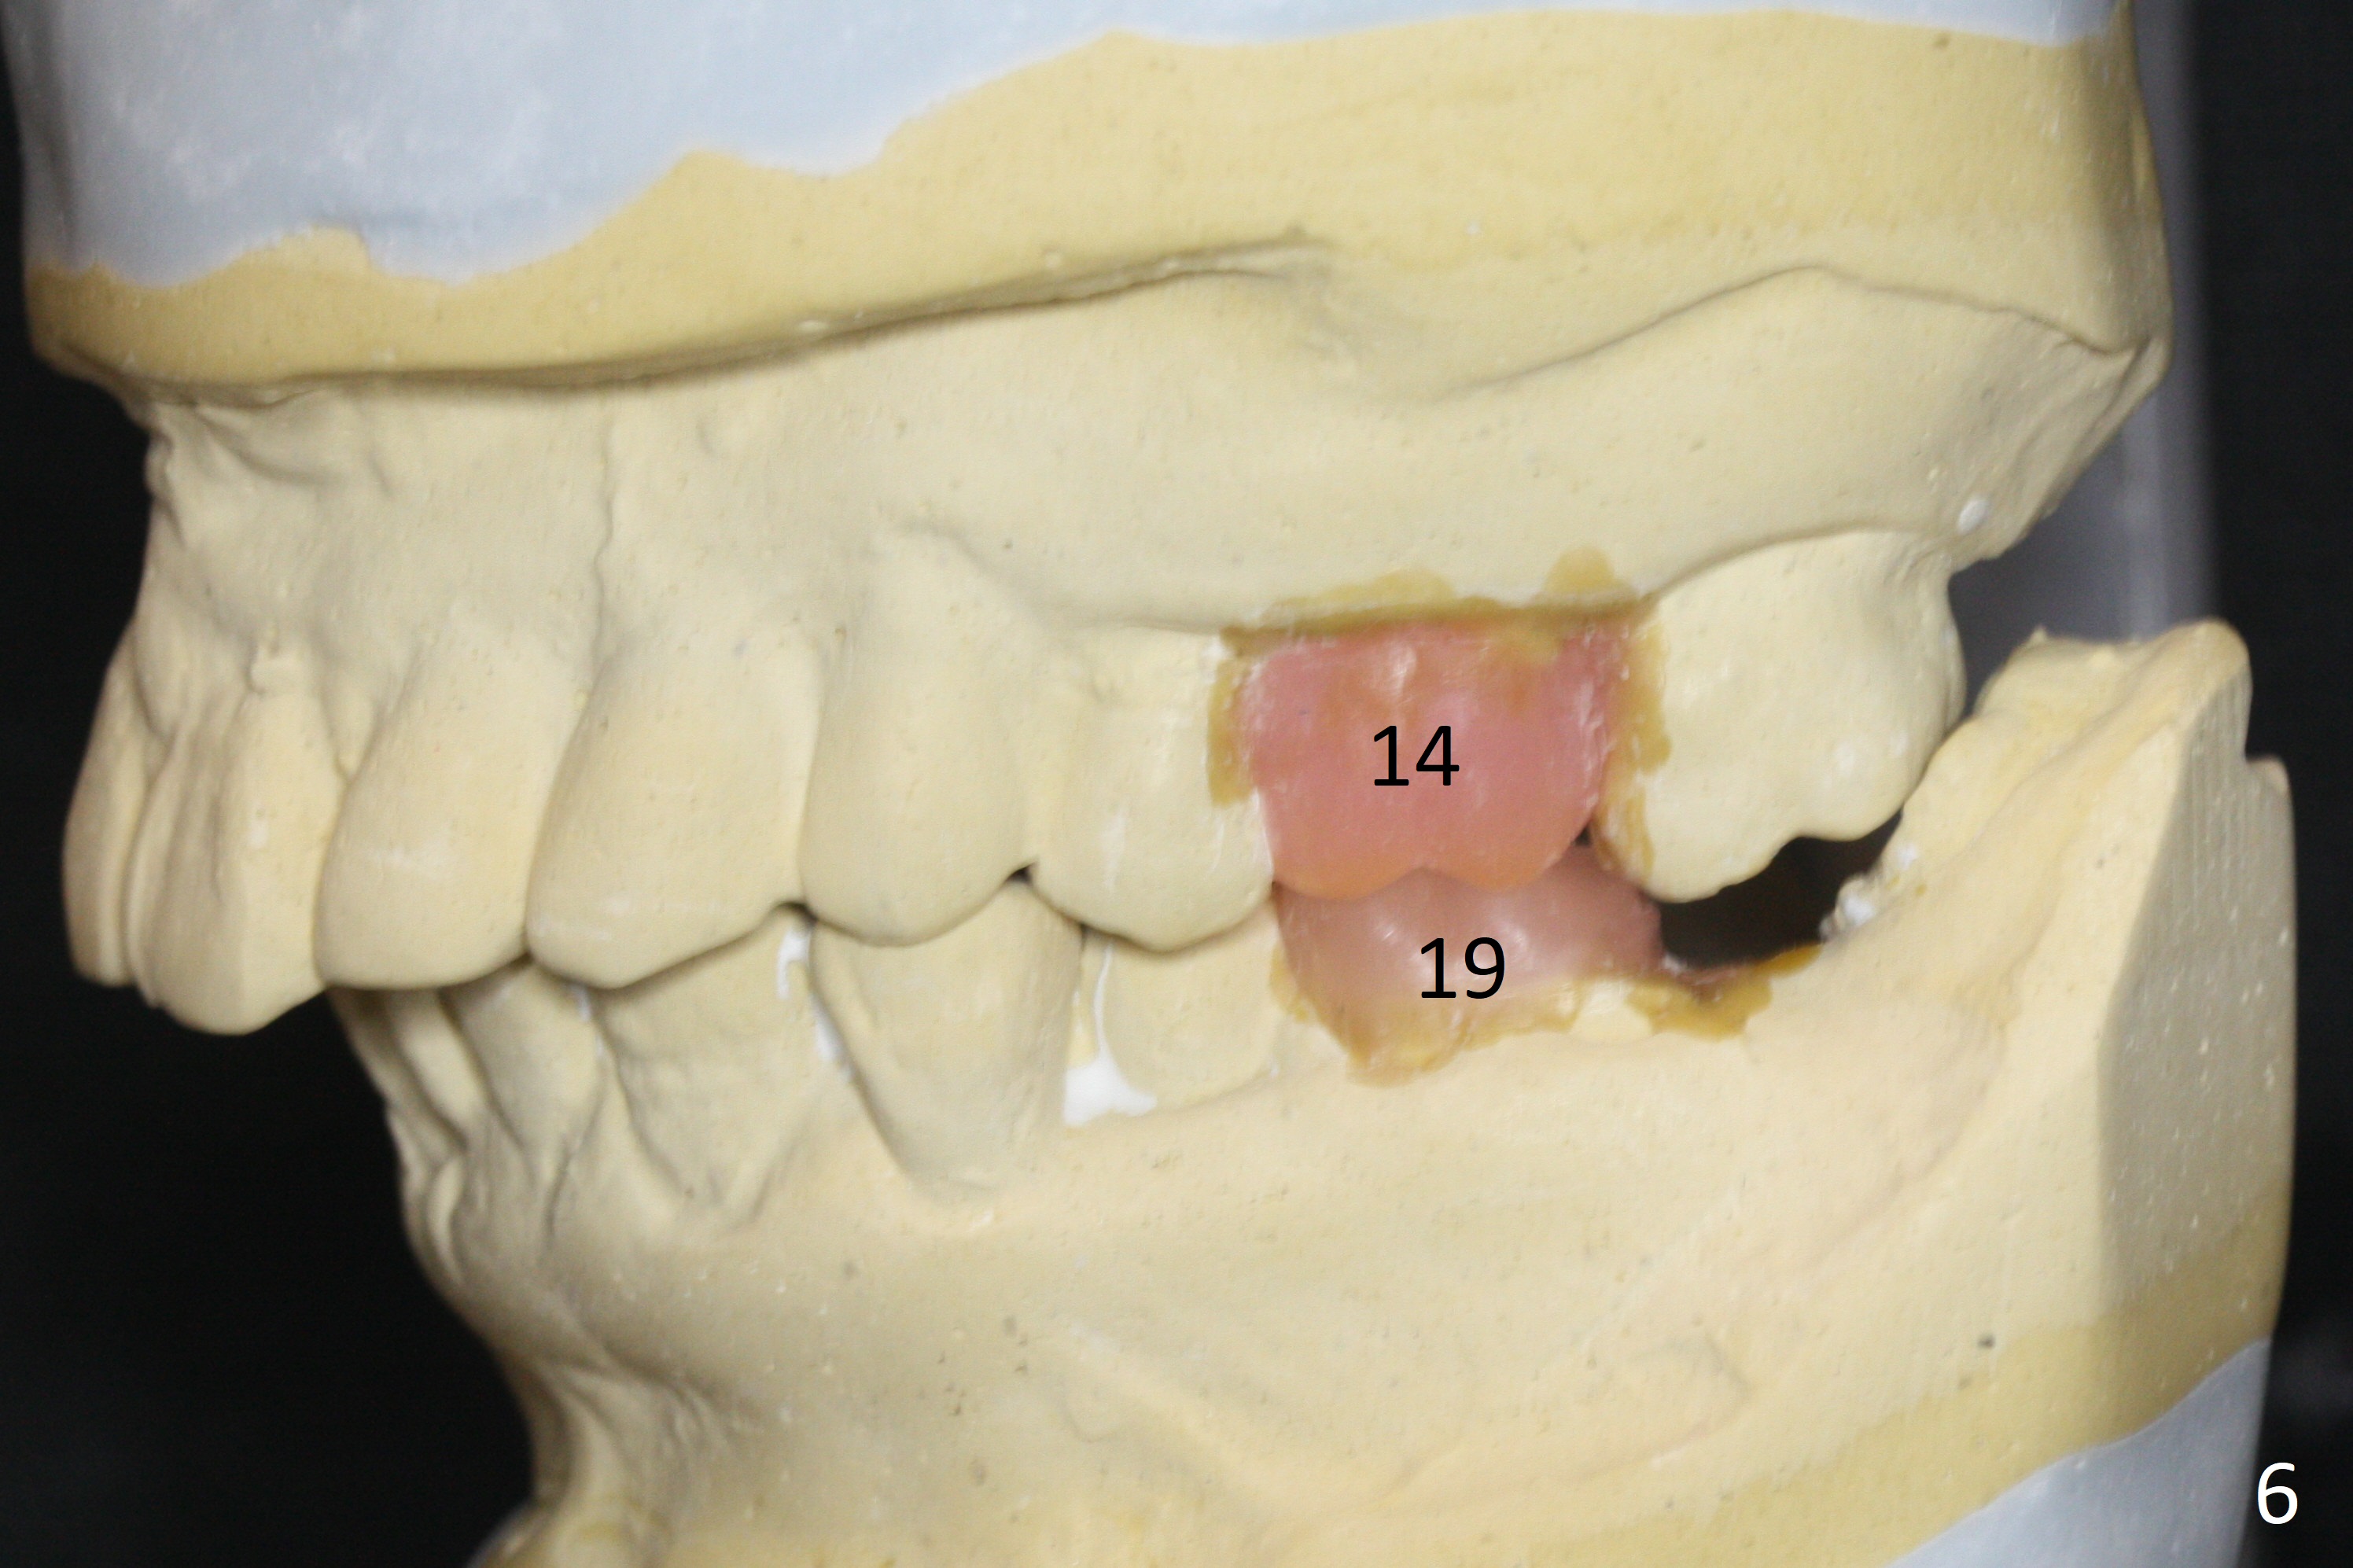

A 54-year-old man is 5 years post liver cancer surgery. After his platelet count returns normal, he wants to take care of his teeth. Most of his molars (#14, 19, 30,31) need extraction and implant placement (Fig.1-4). Although the 2nd premolars on the right are missing (Fig.1,3,4), it seems appropriate to establish 2 molar occlusion on the right (Fig.5,7,8) and 1 on the left (Fig.6,7 (because of #15 supraeruption (Fig.2 arrow))) . Since the residual roots in the lower right quadrant are irritating, implant placement will be done first (Fig.11, Clindamycin), followed by #2,3 (Fig.10) and 14(Fig.12 IBS) and 19 (Fig.12). Use IS drills and 4 and 5 mm stoppers to start osteotomy at #30 and 31, respectively.